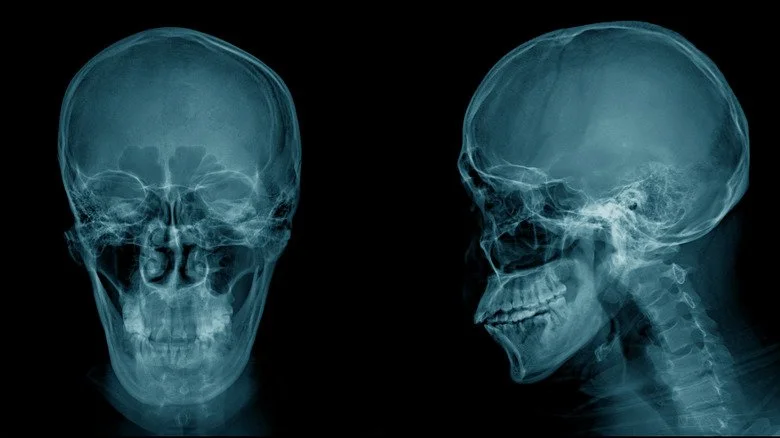

Un des premiers xénotransplantations documentés a été réalisé par le chirurgien persan Muhammad Baha’ al-Dawla. Dans son ouvrage « La Quintessence de l’Expérience », publié en 1501, al-Dawla décrit comment il a traité une ostéomyélite du crâne en remplaçant l’os malade par un morceau d’os provenant d’un chien. « Une tranche de concombre a également été utilisée pour protéger le cerveau », selon des sources sur la xénotransplantation.